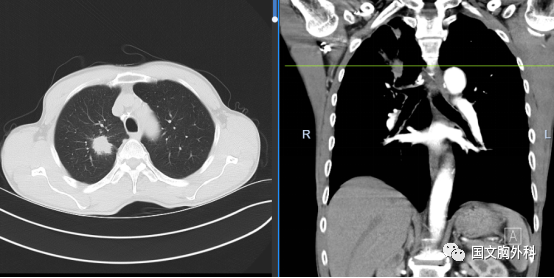

周大爺,發(fā)現(xiàn)肺占位1個(gè)月。CT下觀察右肺上葉腫物延續(xù)至肺門(mén),穿刺病理提示:肺鱗癌。有手術(shù)機(jī)會(huì),家屬同意手術(shù)治療。

術(shù)中患者右肺門(mén)分離困難,決定行右肺上葉袖型切除,在長(zhǎng)達(dá)8小時(shí)的奮斗后,周大爺手術(shù)順利結(jié)束。